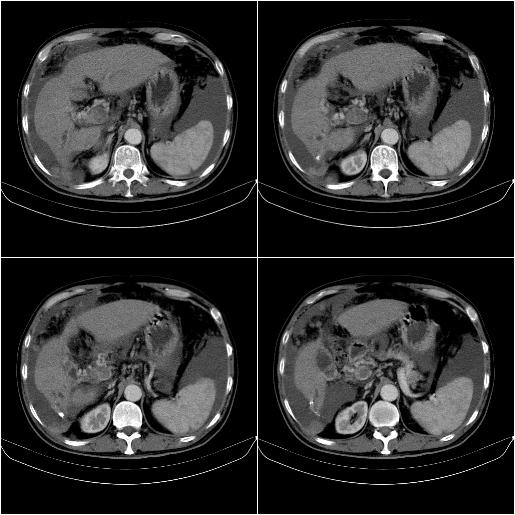

标题: CT21651:M,67Y,肝癌9月,介入术后3月。

m,67y,肝癌9月,介入术后3月。现腹胀、纳差、腹泻。

门静脉有很大的瘤栓,膈肌及膜膜有转移,不用再做了.

情况不好,门静脉癌栓、腹膜转移。

1)肝癌介入治疗术后碘油沉积不良。2)门静脉瘤栓形成,腹膜广泛性转移。3)肝硬化,脾大,腹水。4)慢性胆囊炎。